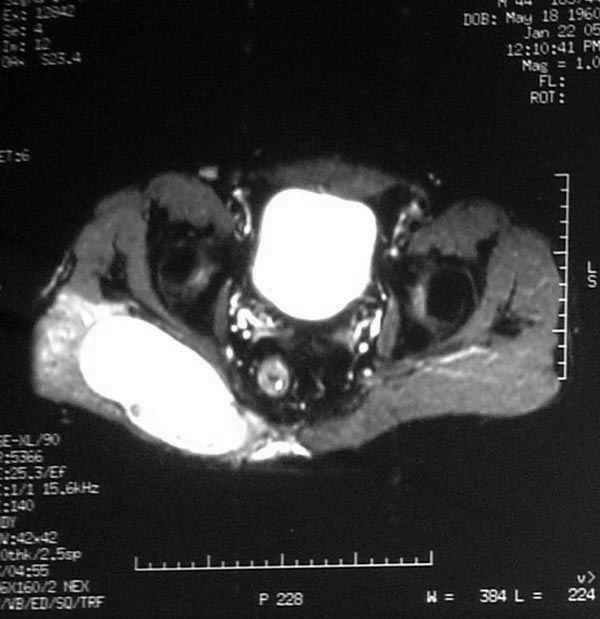

Уважаемые коллеги,Неоднократные пункционные эвакуация (3 раза) крови изягодичной области, после полученной пройзводственнойтравмы (более 1.5 мес) ударом в ягодицу тяжелым, около полутонны предметом.

Рентгенограмма без особенностей, несмещенные переломы лонной и седалищных костей таза.Последная пункция 10 дней назад 180 мл темной крови, после пункции сделано магнито-резонансные исследование (на снимках), какой диагноз и тактика дальнейшего лечения, какие рекомендации?Джолдас Кульджанов

Djoldas Kuldjanov, M.D. 06 Март 2005, 00:25

Разбираемый случай немного отличался от классического Degloving Injury

или Morel-Lavalle Lesion, которые часты при переломах ацетабулума и

костей таза. Состояние, наблюдаемое после удара, в результате чего

образуются обширные полости в тазобедренной области: ягодицы или

большого вертела. Как описал Анатолий, обширные полости заполняются

кровью, затем синовиальной жидкостью, отодвигают сроки операции или

после операции приводят к осложнениям послеоперационных ран.

Лечение повреждений Morel-Lavalle проводится в условиях операционной,

через 3-4 дня после травмы, из маленького (2-3 см) разреза производят

эвакуацию густой пастообразной гематомы, полость промывается и

очищается щеткой изнутри, затем закрывают рану с дренажом, обычно

через 4-5 дней полость затягивается.

Описанный случай:

В промежутке около месяца 3 пункции с удалением около 180 мл крови

каждый раз. После исследовании МРТ было принято решение - удаление

гематомы в операционной более широким доступом. Во время операции -

под ягодичной мышцей была капсула, где скопилось около 700 мл

гематомы, после удаления в полости обнаружили несколько закупорившихся

вен и краевой разрыв одной из двух ветвей нижней ягодичной артерии.

После промывания, гемостаза и дренажа, по рекомендации хирурга стенку

полости обработали спреем Tisseel, специальным склерозирующим

препаратом, применяемым пластическими хирургами, затем зашили рану.

Дренажи удалены на 5 день, рана зажила первично. Случай был интересен

применением препарата Tisseel Fibrin Sealant для склерозирования

полостей, только недавно получившим разрешение к применению, хотя по

аннотации в Европе и в Южной Америке применяют давно.